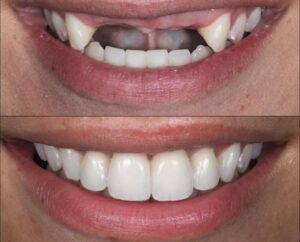

أسنان جديدة تدوم إلى الأبد

يترأس مراكزنا فريق مختار بعناية من خبراء زراعة الأسنان. وبعد عملية الزرع يتم تركيب التيجان والجسور ، والتي يتم تصميمها بأقصى قدر من الدقة والجمالية لمنحك الابتسامة المثالية.